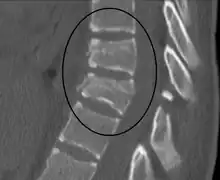

| A Chance fracture of T10 and fracture of T9 due to a seatbelt during an MVC. | |

A CT scan of the chest, abdomen, and pelvis is recommended as part of the diagnostic work-up to detect any potential abdominal injuries.[5][10] MRI may also be useful.[10] The fracture is often unstable.[1]